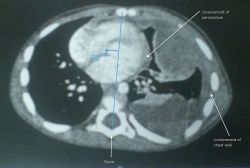

תמונת CT מסומנת של סרקומה של רקמות רכות לא מובחנת בריאה השמאלית של ילד צעיר, המראה מעורבות של קרום הלב ודופן החזה, ותזוזה מדיאסטינלית